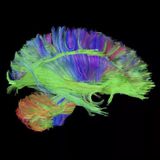

Porphyria

porphyria or ‘the vampire disease’ is an inborn error of metabolism characterized clinically by skin photosensitivity, hypertrichosis, and reddish brown staining of the primary teeth(as shown above). This disease has often been associated with so-called ‘living vampires’. because it has such distinctive symptoms. The disease typically affects the nervous system and skin. The cause is from a lack of heme which is mainly found in red blood cells.